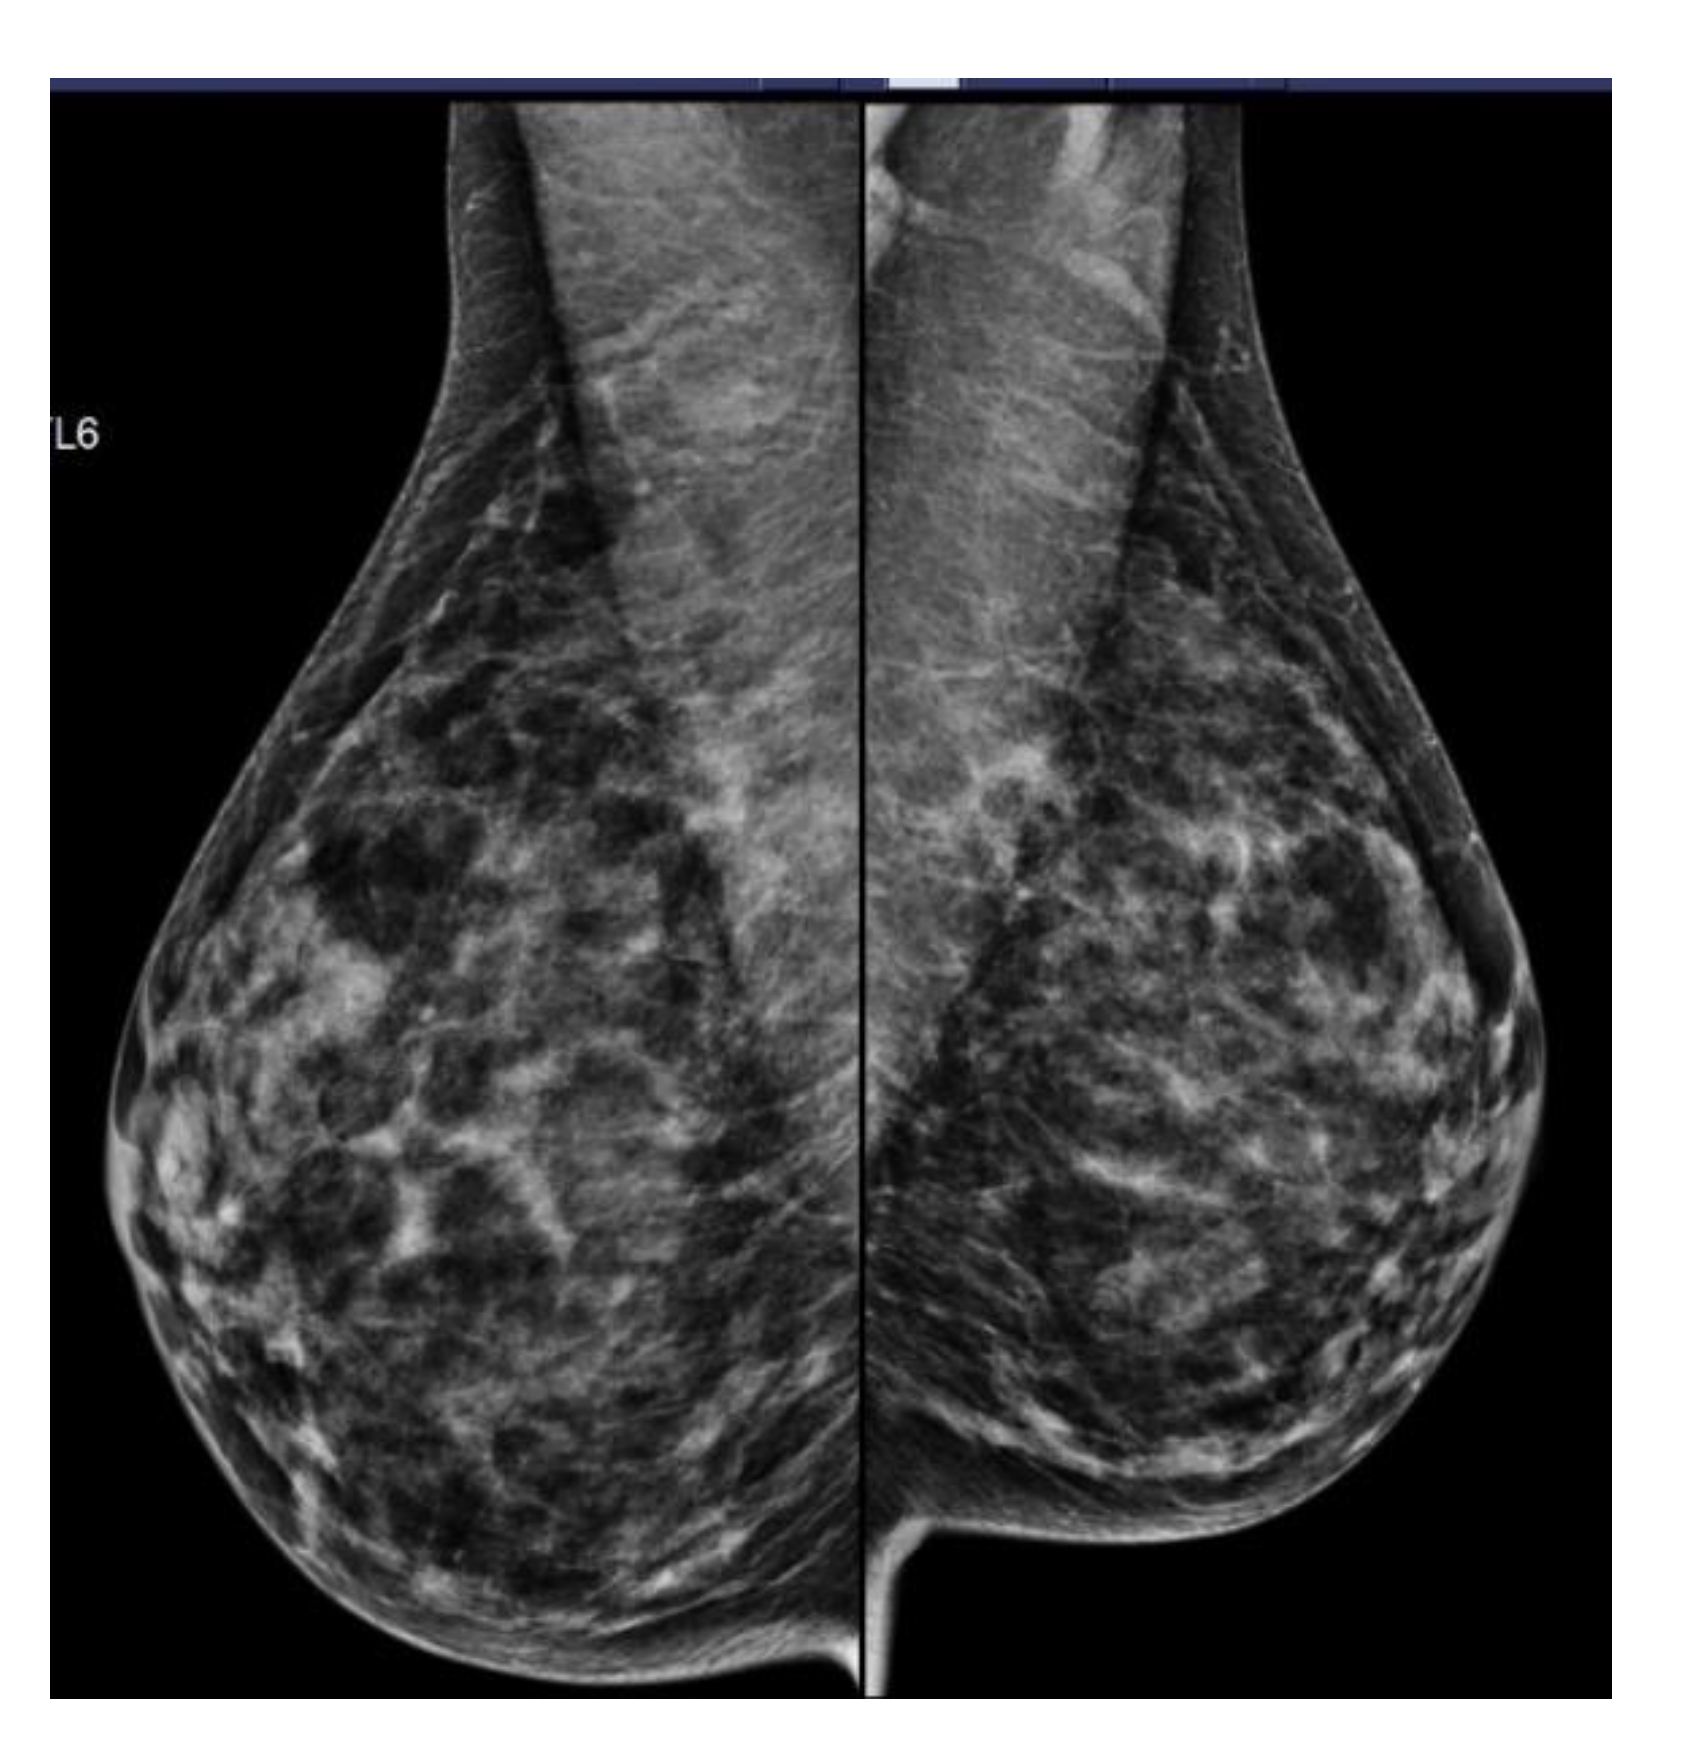

| Density Category | Total Women with Mammograms (% of Total) | Became Eligible (% of Women with Density Category) * | Became Ineligible (% of Women with Density Category) |

|---|---|---|---|

| Density A | 10 (7.6%) | 0 (0%) | 2 (20.0%) |

| Density B | 40 (30.5%) | 0(0%) | 6 (15.0%) |

| Density C | 58 (44.3%) | 5 (8.6%) | 5 (8.6%) |

| Density D | 23 (17.7%) | 4 (17.4%) | 0 (0%) |

| Total | 131 | 9 (6.9%) | 13 (9.9%) |